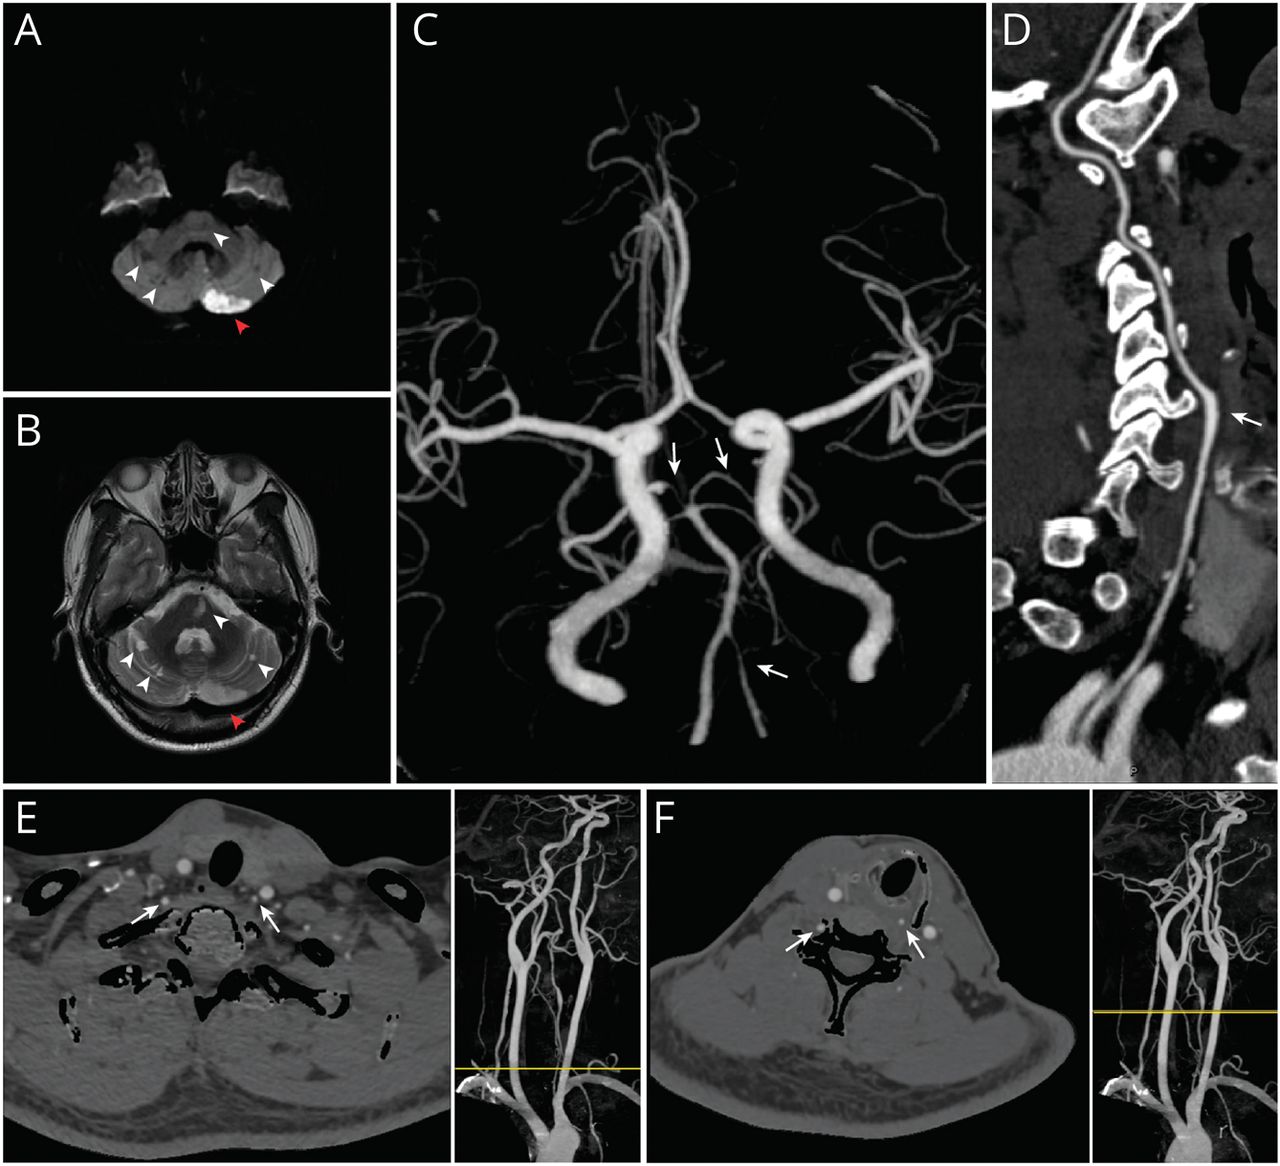

• Brain MRI and CT Angiographies of the Patient Diffusion-weighted imaging showing diffusion restriction in the left cerebellar hemisphere suggestive of acute infarction (A, red arrowhead). T2-weighted image showing multiple areas of hyperintensity in the bilateral cerebellar hemispheres and pons suggestive of chronic ischemic changes (B, white arrowheads). Head CTA revealing a patent but hypoplastic left VA (C, leftward arrow) and dominant right VA in comparison. Note the stenosis in the P1 segment of the right posterior cerebral artery and in P1 and P2 segments of the left posterior cerebral artery (C, downward arrows). Neck CTA showing that the left VA aberrantly originates from the aortic arch between left carotid artery and left subclavian artery and dilates at the C5 cervical level (D, white arrow) then enters the C4 transverse foramen, rather than the typical C6 level. The axial planes of CTA showing asymmetrical VAs in either V1 segment (E, white arrow) or V2 segment (F, white arrow). Yellow lines in the right panels indicate the corresponding transverse levels.

图1 患者脑部MRI及CT血管造影术

扩散加权成像显示左小脑半球扩散受限,提示急性梗死(A,红色箭头)。t2加权图像显示双侧小脑半球和脑桥多发高强度区,提示慢性缺血性改变(B,白色箭头)。头部CTA显示未发育但发育不良的左VA (C,左箭头)和显性右VA。注意右侧大脑后动脉P1段和左侧大脑后动脉P1和P2段的狭窄(C,向下箭头)。颈部CTA显示,左VA异常起源于左颈动脉和左锁骨下动脉之间的主动脉弓,在C5颈段(D,白色箭头)扩张,然后进入C4横孔,而不是典型的C6颈段。CTA轴向面显示V1段(E,白色箭头)或V2段(F,白色箭头)VAs不对称。右侧面板中的黄线表示相应的横向水平。